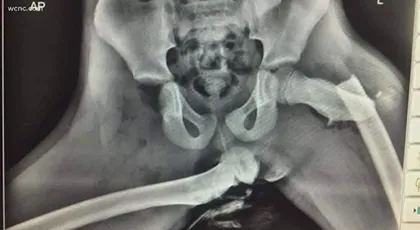

X-Ray Shows Severe Injuries After A Crash

An X-ray photo shared worldwide showed the injuries of a young woman who had her feet on the dashboard during a crash.

Doctors said the crash completely dislocated her right hip and pushed her left thigh bone through the skin. Troopers in North and South Carolina confirmed it’s not illegal to ride with your feet up, but they strongly warn against it.

Doctors believe the airbag caused the majority of her injuries and said crashes like this could require hip replacements or cause long-term conditions like post-traumatic arthritis.